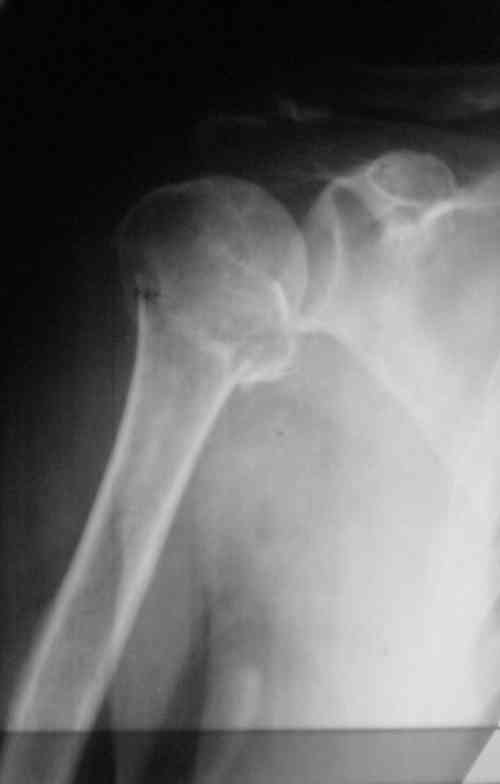

Судя по снимкам головка ротирована,успех закрытой репозиции, на мой взгляд, сомнителен, надо оперировать.

Судя по Р-граммам имеется оскольчатый перелом головки плеча. Во время открытой репозиции имеется большой риск "развалить" перелом, что значительно ухудшит кровоснабжения отломков. А так, на мой взгляд контакт м\у отломками достаточный, не смотря на наличие ротационного смещения головки думаю лучше продолжать консерватикное лечение. С уважением.

Судя по снимкам еще имеется перелом головки плеча, и чрезкостный отрыв вращательной манжеты. Для уточнения характера перелома не иешало бы сделать КТ. Если вести консервативно, то после сращения перелома будет ограничение движений в суставе не устраивающее больную. Я склоняюсь к оперативному лечению( накостный остеосинтез Т- Г образная пластина, лучше LCP для проксимальног плеча, обязательно подшить на место манжету).

В соответствии с работами Neer данный перелом можно классифицировать как однофрагментарный, так как нет диастаза более 1 см и углового смещения более 45 градусов - такие переломы лечатся консервативно. Рентген контроль каждые 10 дней- если смещение не увеличивается, то через 3-4 недели разработка движений в суставе

Уважаемый Сергей! Вы правильно написали критерии, но недооценили степень смещения в переломе хирургической шейки. Посмотрите ещё раз, это Two part fracture.